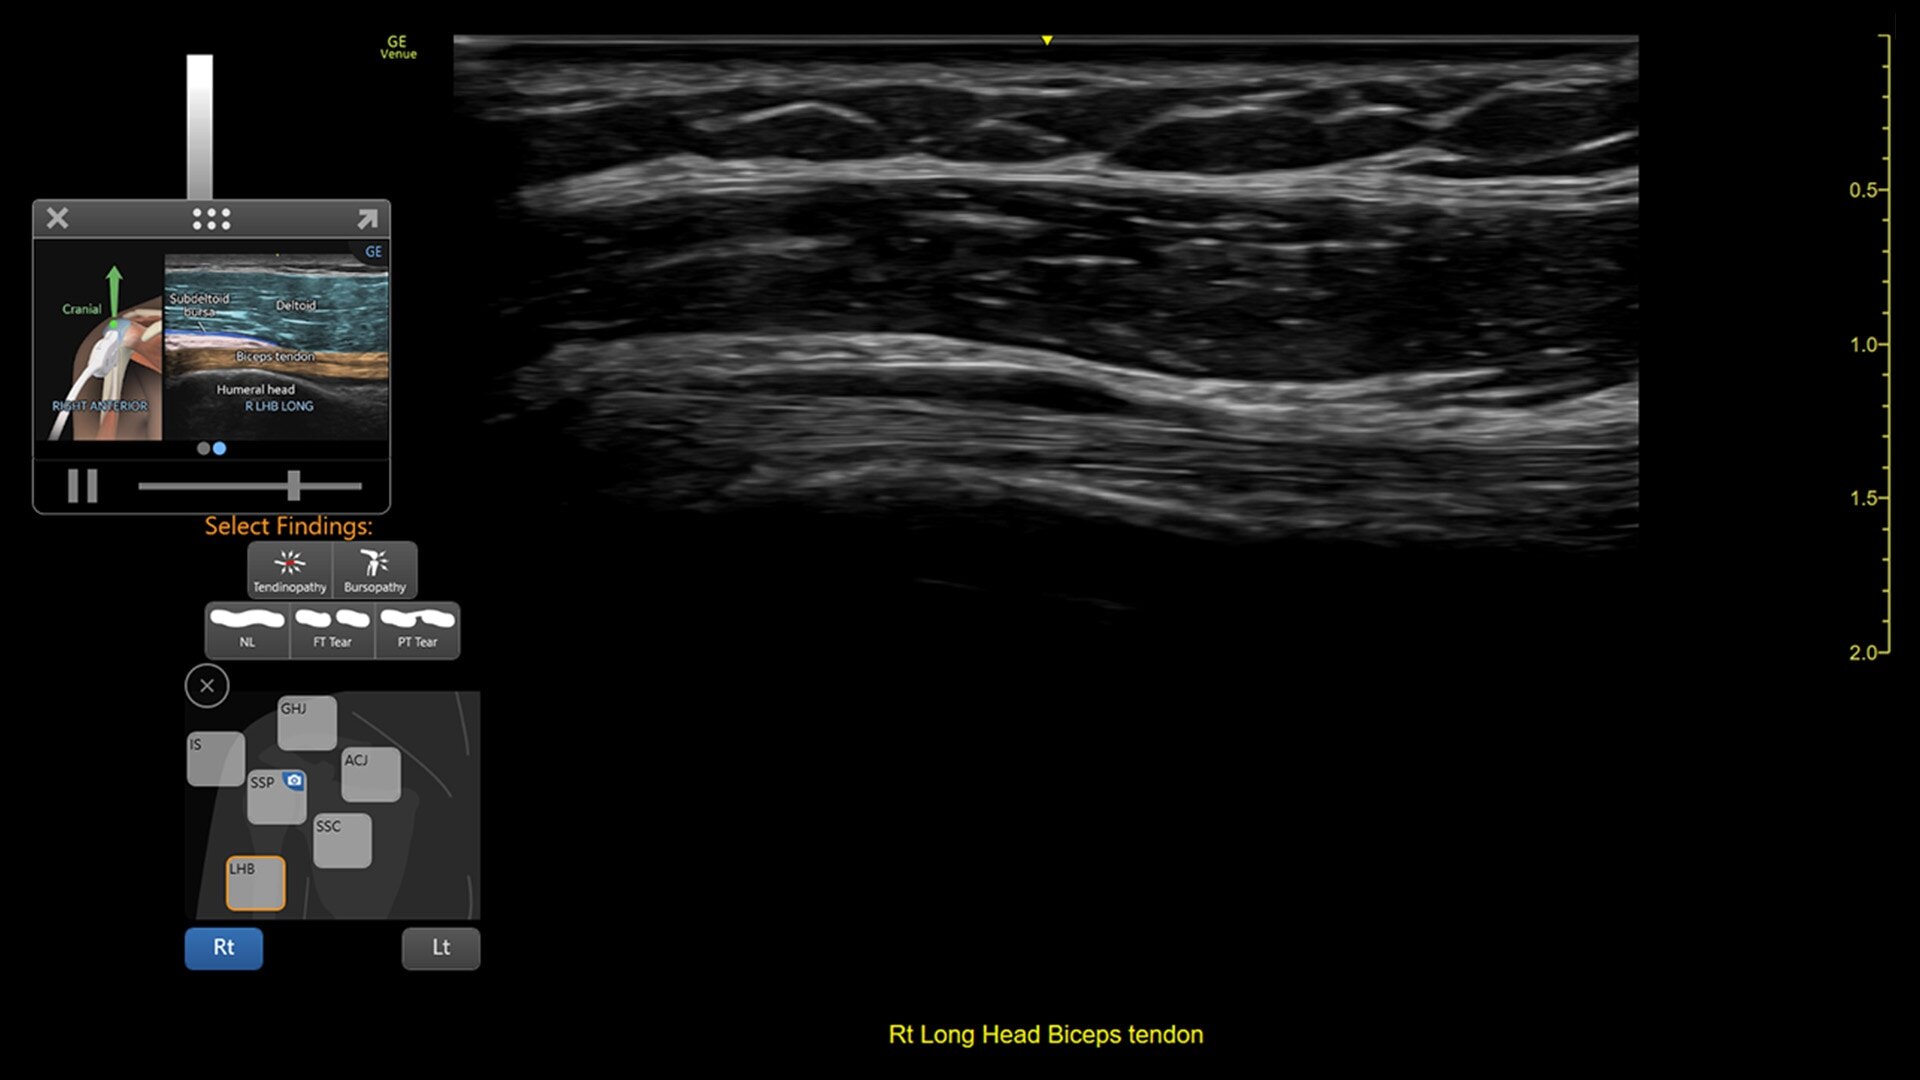

Venue Coach MSK

Simplifying MSK scans

This easy-to-use exam documentation tool assists users through exams by providing reference images and anatomy markups. Multiple anatomical areas and helpful video tutorials help clinicians to acquire the scans they need.

MSK Diagrams: Simplifies documentation and assists the clinician in follow up for patients. No need to manually type findings—you can simply assign a label from a pre-populated list that correlates with the images. Get a single view diagram with one click image storing, keep track of assessments and show trends in response to therapy.

Reference Image: Reference image provides anatomy mark-ups to assist novice users in scanning the correct anatomy